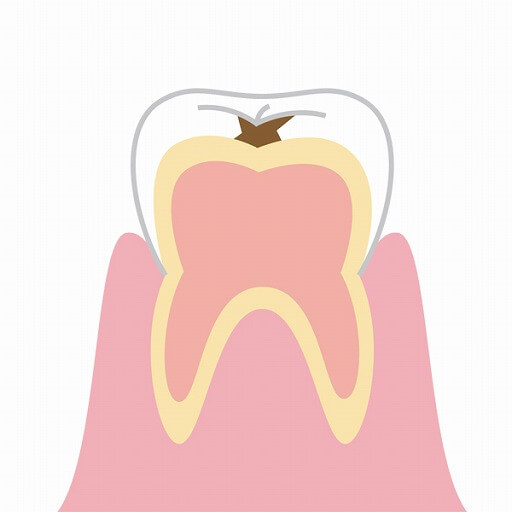

虫歯の進行別治療法

虫歯は、その進行の程度によって症状・治療法が異なります。

「痛み」がある時点で、ある程度進行しています。できる限り予防に取り組みつつ、定期検診で痛みのないうちの早期発見ができるようにしておきましょう。

C2 C2象牙質に 到達した虫歯 |

・冷たいものしみる(冷水痛) ・甘いものがしみる |

虫歯を削り、型取りをして詰め物を作製し、取り付ける。被せ物が必要になることも。 |

C3 C3神経に 到達した虫歯 |

・常時のズキズキとした痛み |

根管治療を行った上で、型取りをして被せ物を作製し、取り付ける。 |

C4 C4歯の根に 到達した虫歯 |

・歯の見えていた部分のほとんどが溶けてなくなる ・神経が死ぬと痛みが消失、その後歯の根の炎症で痛みが激しく再発 |

歯を残すことが難しい場合には、抜歯となることが多い。 ただし、歯茎より下の部分に健康な歯の質が残っている場合には、外科処置や矯正処置を行うことで保存できる場合もある。 抜歯した場合には、ブリッジ、入れ歯、インプラントなどの治療を行う必要がある。 |